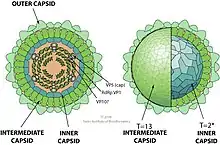

| Coltivirus virion.[1] | |

The Coltivirus virions are about 60-80 nanometers in diameter and are not enveloped, and are generally a spherical shape with icosahedral symmetry. Each virion has two concentric capsid shells surrounding a core of about 50 nanometers in diameter. The surface of the particle is relatively smooth.[7] The virus loses its infectivity when the surrounding fluid becomes acidic, around a pH of three, but is stable when the pH is between seven and eight. It also stops being a threat when the temperature becomes about fifty-five degrees Celsius.[7]

| Coltivirus | Icosahedral | T=13, T=2 | Non-enveloped | Linear | Segmented |